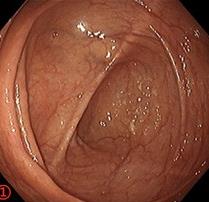

摘要:目的 探讨利那洛肽联合西甲硅油与复方聚乙二醇电解质散(PEG)对便秘患者肠道清洁效果的有效性和安全性。方法 采用前瞻性随机对照试验,通过单盲法,纳入2023年4月-2024年8月于该院消化内镜中心行结肠镜检查的便秘患者383例,随机分为常规组(128例)、实验A组(128例)和实验B组(127例)。常规组采用3 L PEG(Ⅰ)溶液,实验A组采用290 μg利那洛肽 + 2 L PEG溶液,实验B组采用290 μg利那洛肽 + 30 mL西甲硅油+2 L PEG溶液。比较3组患者的肠道准备效果[Boston肠道准备量表(BBPS)评分和去泡效果]、病变检出率、首次排便间隔时间、排便次数、盲肠插管成功率、进镜时间、退镜时间、不良反应发生率和重复检查意愿等。结果 3组患者BBPS评分比较,差异无统计学意义(P > 0.05);实验B组的去泡效果评分明显低于常规组和实验A组,差异均有统计学意义(P < 0.05);实验B组的病变总检出率和息肉检出率明显高于常规组和实验A组,差异均有统计学意义(P < 0.05);常规组的首次排便间隔时间明显长于实验A组和实验B组,差异均有统计学意义(P < 0.05);3组患者排便次数比较,差异无统计学意义(P > 0.05);3组患者盲肠插管成功率均为100.0%,进镜时间相当,差异均无统计学意义(P > 0.05);实验B组的退镜时间明显短于常规组和实验A组,差异均有统计学意义(P < 0.05);常规组腹胀腹痛发生率和不良反应总发生率明显高于实验A组和实验B组,差异均有统计学意义(P < 0.05);常规组重复检查意愿率明显低于实验A组和实验B组,差异均有统计学意义(P < 0.05)。结论 290 μg利那洛肽联合30 mL西甲硅油与2 L PEG溶液方案在便秘患者肠道准备上具有优势,较3 L PEG溶液和290 μg利那洛肽+2 L PEG溶液方案,可获得更好的肠道清洁效果,且安全性和患者重复检查意愿率高,可作为便秘患者肠道准备的推荐方案。